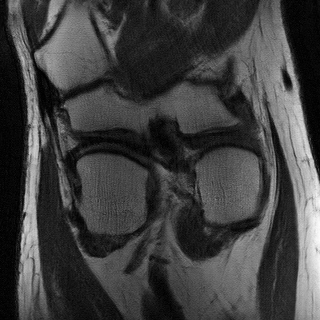

4.4 Qualitative Evaluation

In Figure 5 we analyze the prediction quality of our and compared approaches in a qualitative way. Considering modality propagation in MRI, we see that usage of uncertainty-aware patch invariance (UAPI) gives a better detailed weighting of the cerebrospinal fluid in the middle of the brain. In general, employing patch invariance yields better preservation of fine structures. This observation also applies to accelerated MRI enhancement. In particular, CUT and UAPI provide comparatively sharper knee images with more high-frequency details than the other methods.

Additional to improved accuracy we demonstrate the efficacy of estimating the scale maps with the proposed method. The input-dependent non-negative scale maps are derived from the second output branch , see (9). Indeed, the predicted scale maps are able to model uncertainty inherent from data. This can be observed in Figure 8, where in addition to the transferred images also the predicted scale maps and the absolute residuals between predicted and ground truth images are displayed. Obviously, uncertainty is relatively greater in regions with higher residual values. From the scale maps it can be deduced for which positions the generator is comparatively uncertain in its prediction, such as the cerebral cortex and eye sockets in head MRI or the lateral knee ligaments in knee MRI.